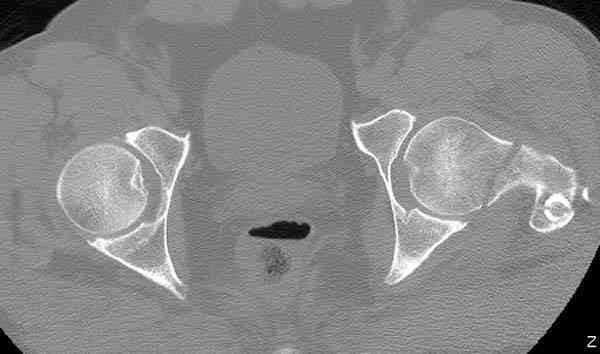

Кроме обязательных ренгенологических снимков тазобедренного сустава, при подозрении на перелом шейки рекомендуем Компьютерную Томографию.

Здесь представлены снимки больного 65 лет, поступившего с диагнозом перелом

бедра после автоаварии.

В первый же день произведено антеградное штифтованием DePuy Trochanteric Nail.

На второй день (7) обнаружен пропущенный перелом,

сделаны Компьютерная Томограмма

и проведены шурурпы через и спереди штифта без удаления.

Послеоперационные снимки